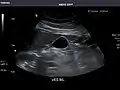

Aorta